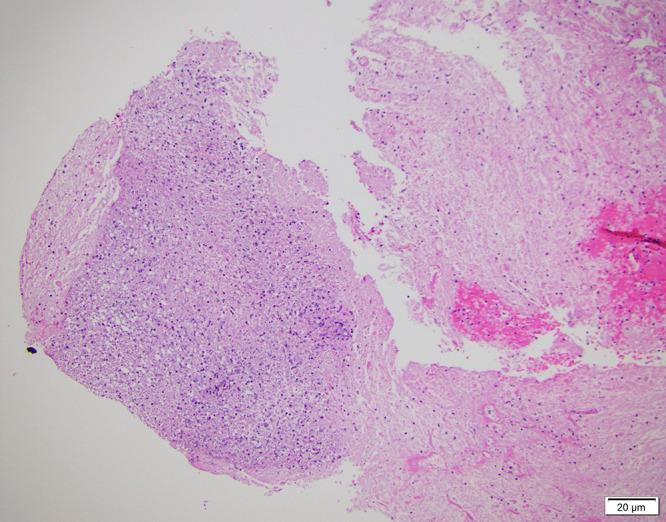

Nocardia cyriacigeorgica represents a rare cause of cerebral abscesses. Rarer still are brainstem abscesses caused by this bacterial species in immunocompetent hosts. In fact, only one such brainstem abscess case has been described in the neurosurgical literature to our knowledge to date. Herein, a case of Nocardia cyriacigeorgica abscess in the pons is reported, as well as a description of its surgical evacuation via the transpetrosal fissure, middle cerebellar peduncle approach. The authors review the utility of this well-described approach in treating such lesions safely and effectively. Finally, the authors briefly review, compare, and contrast related cases to this one.